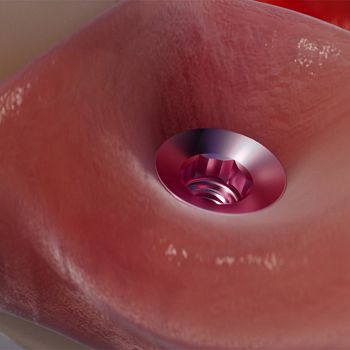

Gestión simplificada del tejido blando para función y estética inmediatas.

Una conexión trata todos los diámetros.

Muñón Cónico Mini